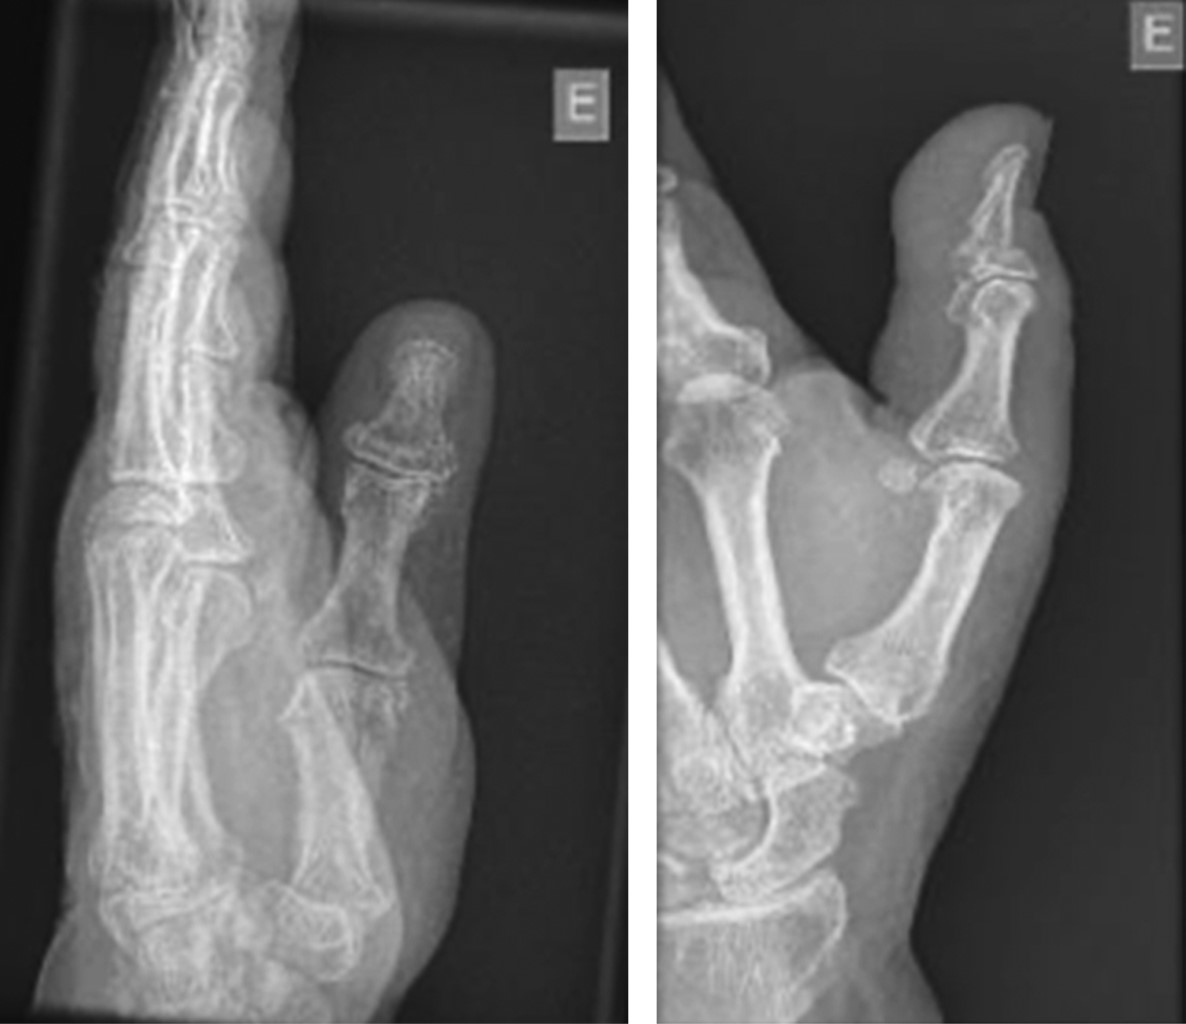

Luxación volar de la articulación metacarpofalángica del pulgar: reducción abierta y reparación del ligamento colateral cubital. Reporte de un caso

Introducción: las luxaciones metacarpofalángicas del pulgar no son lesiones muy frecuentes, es necesario conocer la anatomía de la región para conocer posibles causas de interposición que impidan una reducción cerrada de esta patología. Presentación del caso: presentamos el caso de una mujer de 75 años con luxación metacarpofalángica postraumática del pulgar que requirió reducción abierta y reparación quirúrgica. En este procedimiento realizamos reducción de la luxación, movilización de las estructuras interpuestas, reparación de la cápsula y reinserción del ligamento colateral cubital. El protocolo de movilización temprana ayudó a obtener muy buenos resultados. Conclusión: es imperativo considerar posibles lesiones asociadas durante la fase aguda para lograr resultados óptimos a corto, mediano y largo plazo para nuestros pacientes. Un enfoque integral y proactivo del diagnóstico y tratamiento es vital para abordar eficazmente esta patología y minimizar sus posibles secuelas.

Figura 1